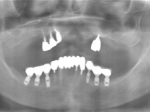

両側5歯症例

両側5歯症例両側5歯症例両側5歯症例 主訴-義歯のバネが壊れて手前の歯が痛んできた。 術前(旧義歯装着、鏡像) 術前(下顎粘膜面、鏡像)術前(下顎粘膜面、鏡像)術前(下顎粘膜面、鏡像) 術前レントゲン術前レントゲン術前レントゲン 術前口腔内(正面観)術前口腔内(正面観)術前口腔内(正面観)

術後(鏡像)術後(鏡像)術後(鏡像) 術後口腔内(正面観)術後口腔内(正面観)術後口腔内(正面観)もう入れ歯は要らなくなりました。 術後レントゲン術後レントゲン術後レントゲン